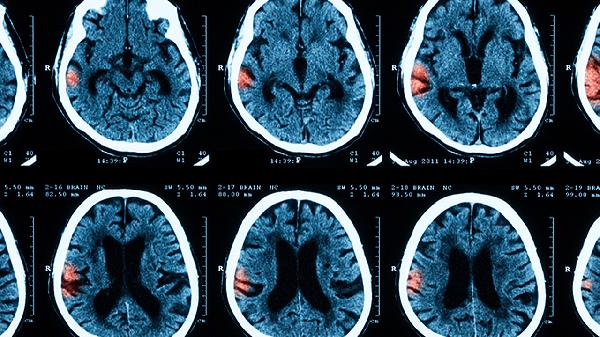

头部CT或MRI检查可排除脑脓肿、脑肿瘤等其他颅内病变。影像学能显示脑膜强化、脑室扩大等脑膜炎特征性改变。严重病例可能出现脑水肿、脑梗死或脑积水等并发症。对于结核性脑膜炎,MRI可发现基底池脑膜增厚和结核瘤形成。影像学检查对评估病情严重程度和预后有重要价值。